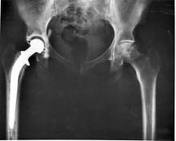

Metal on metal hip resurfacing versus uncemented custom total hip replacement – early results

Hip resurfacing has become more popular in this group following advances in engineering and metallurgy. Modern metal-on-metal bearings appear to offer excellent wear properties when compared to historical resurfacing designs, which were mainly metal-on-polyethylene. HR seems to be an attractive concept which offers durable bearing surfaces with low wear, bone conservation and simple revision options particularly on the femoral side.

The results of our study suggest that the functional outcome of HR is not superior to custom uncemented THA in the short term and should therefore not be used as the sole basis for deciding which of the procedures to undertake in individual patients. It may be that the potential ease of revision and femoral bone conservation in this group is a driver for the choice of implant especially if both treatments are effective with a high degree of patient satisfaction.